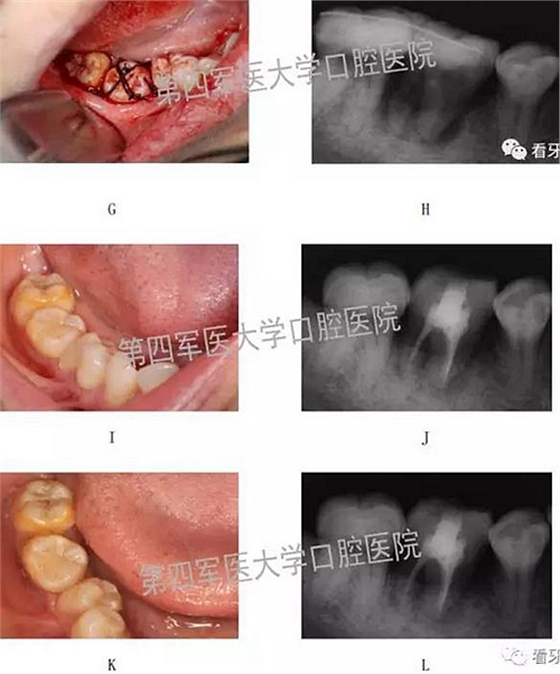

二,牙槽內(nèi)移植

1,阻生牙牽出再值